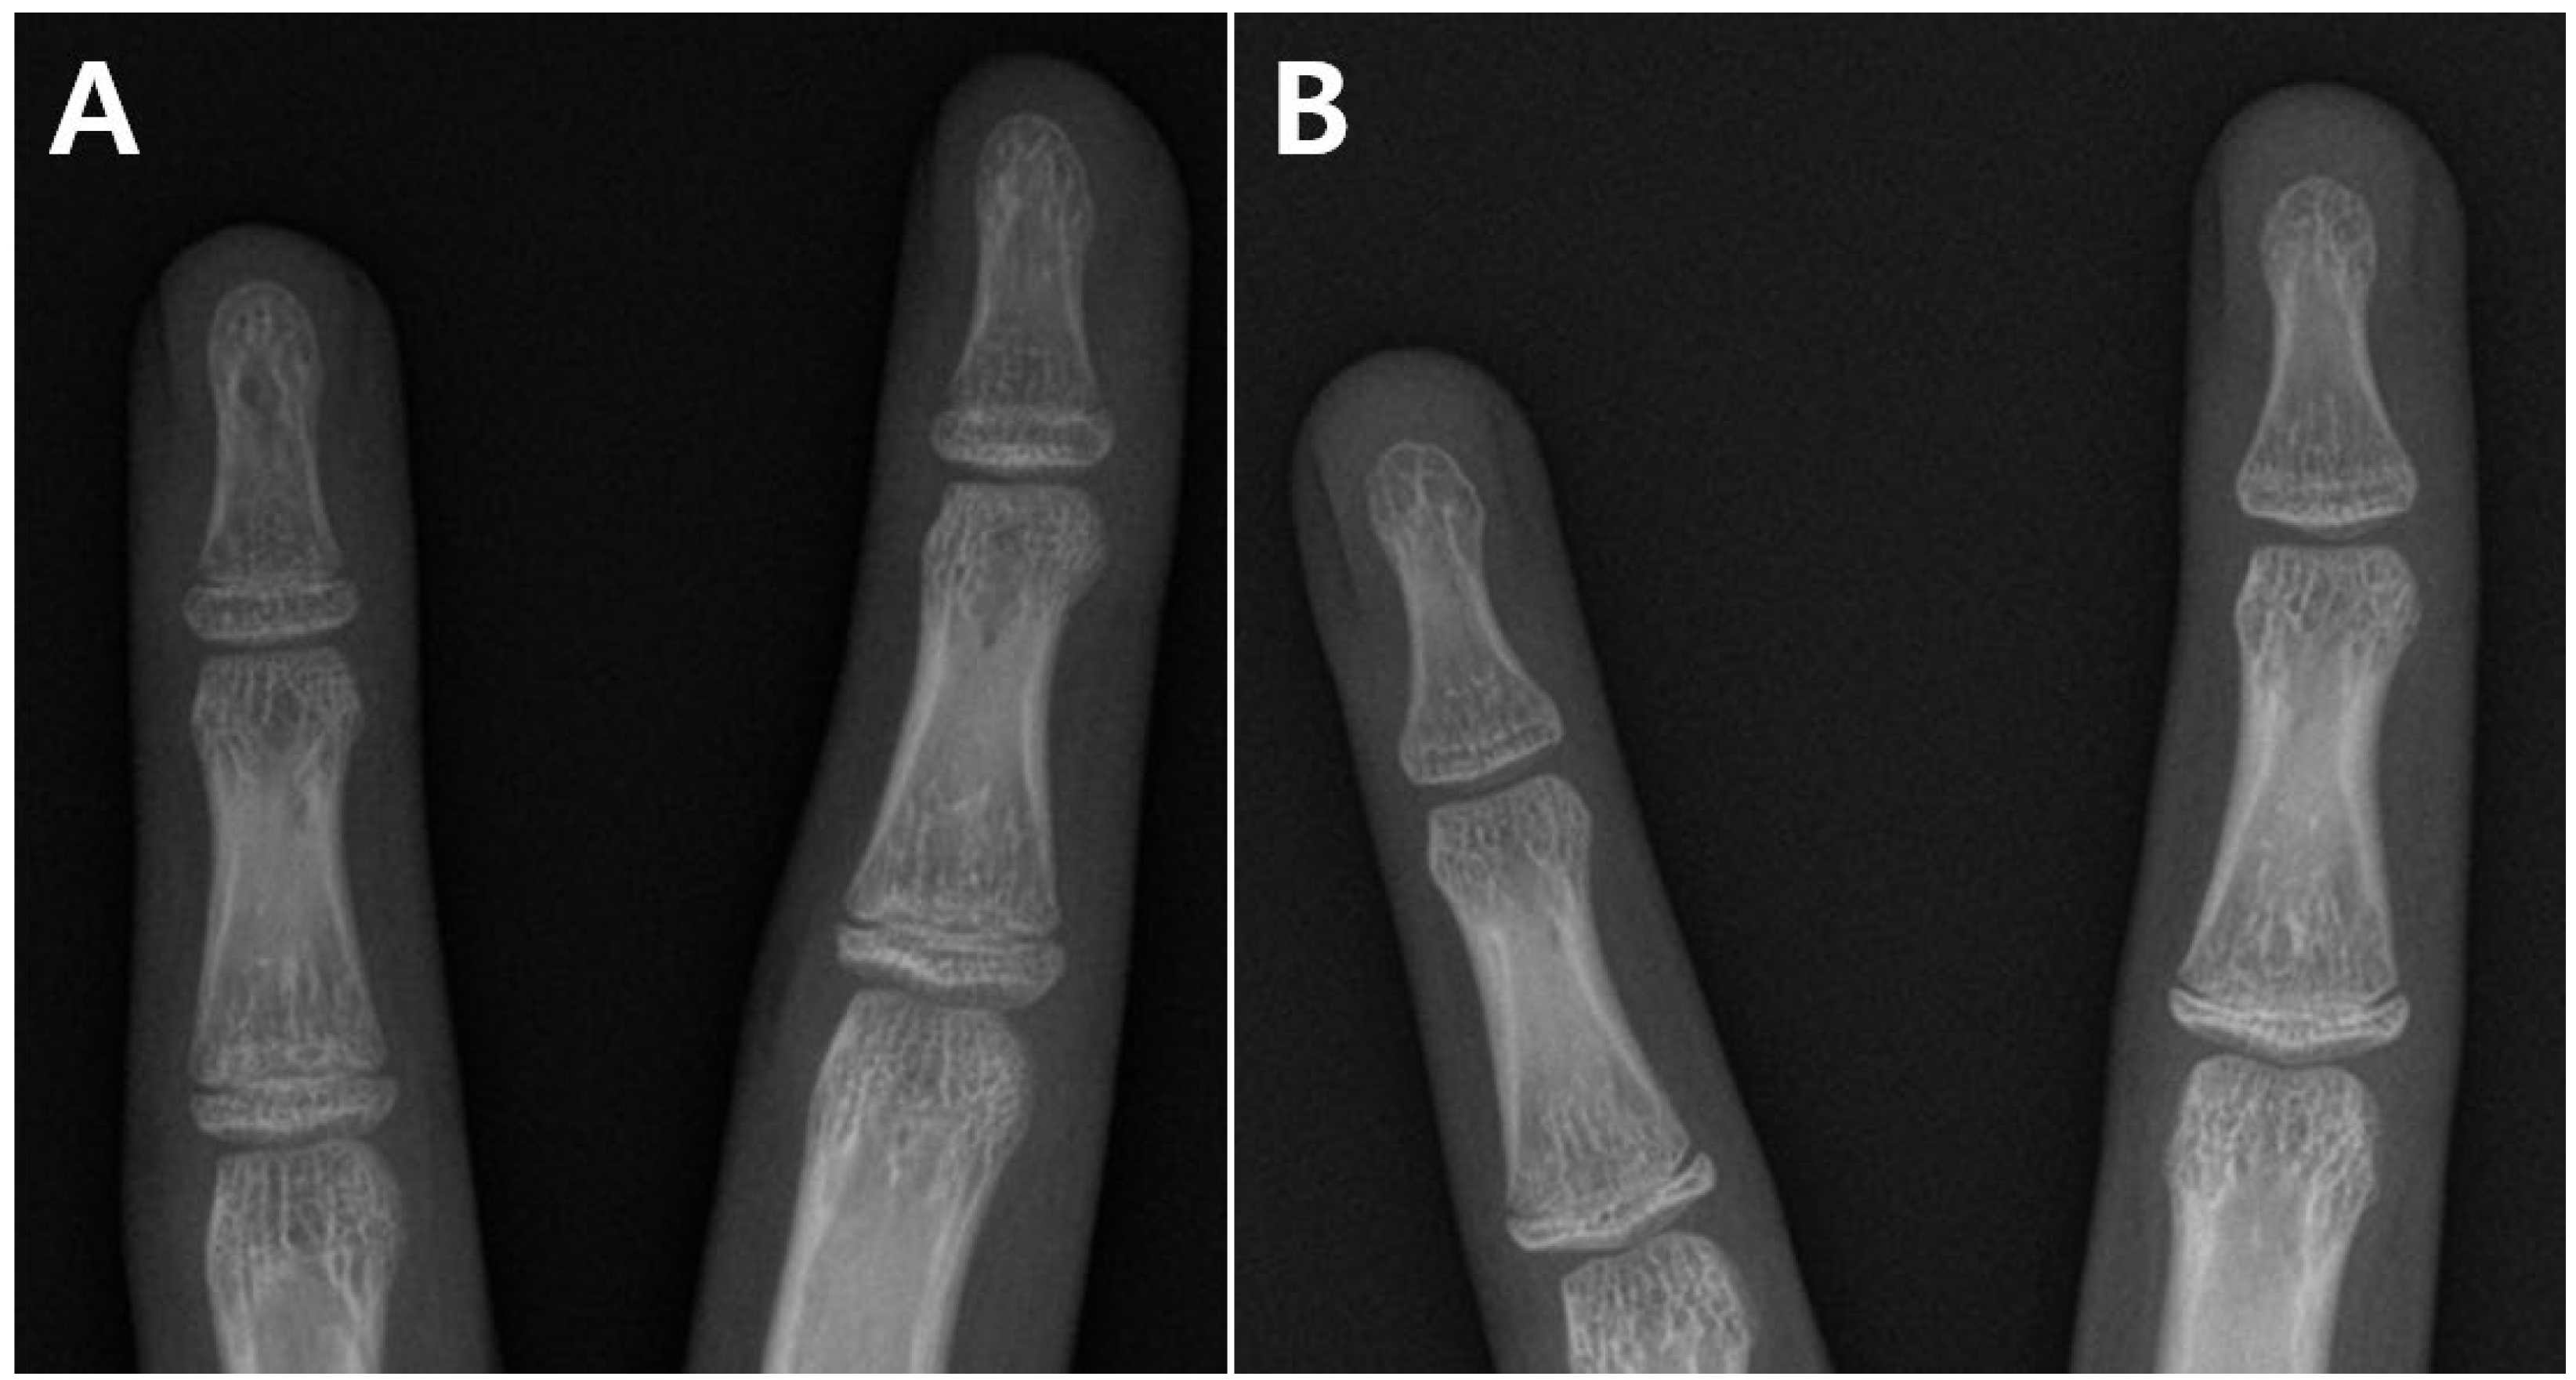

2.2. Surgical Technique

2.3. Radiographic Measurement